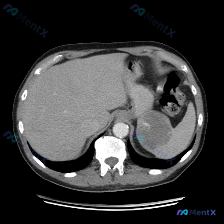

整理了一个脾脏占位的影像资料,结合临床思路梳理了一下分析过程,和大家分享。 先看核心影像表现 这是一份腹部CT横断面(软组织窗,单帧图像)的客观描述: - 肝脏:形态、密度大致正常,未见明确占位。 - 脾脏:这是核心异常——可见一较大类圆形低密度占位,边界相对清晰,但内部密度不均匀,可见部分稍高密度...